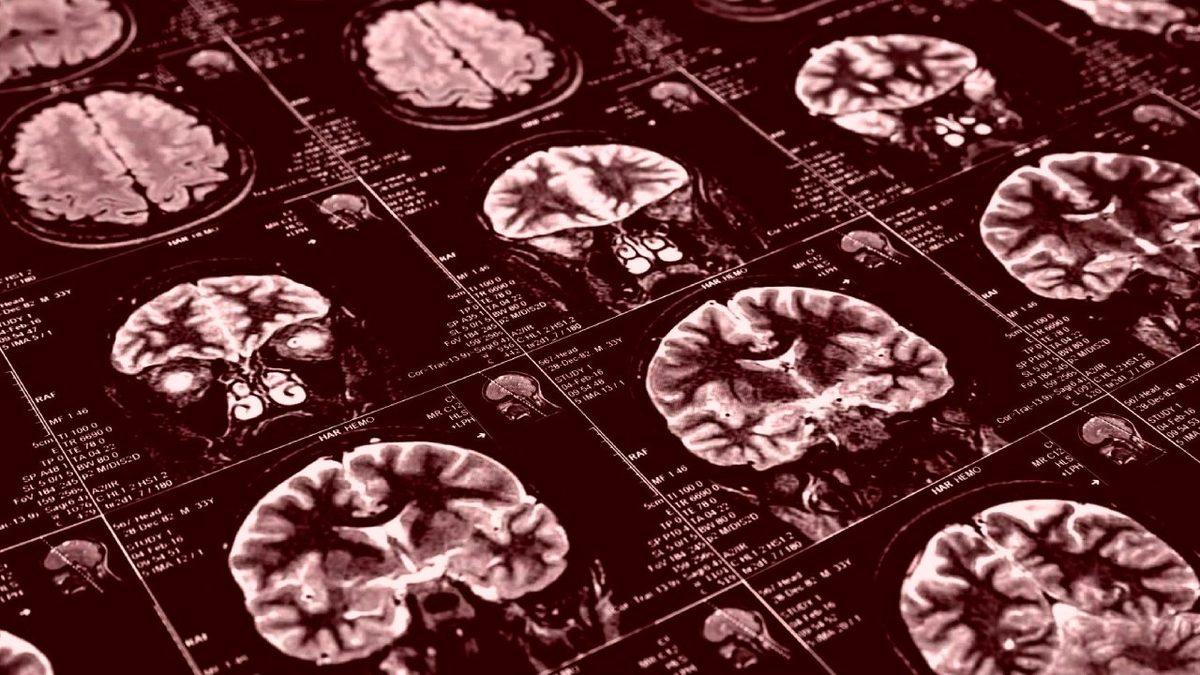

Hakem onayından geçmeyen ve MedRxiv internet sitesinde erişime açılan bir araştırma sonucunda, virüsle enfekte olan hastaların, hastalığı hafif atlatsalar dahi beyinlerinde küçülme meydana geldiği tespit edildi. Araştırmacılar bu çalışma için, 45 bin kişinin COVID-19 pandemisinden önce kaydedilmiş beyin görüntüleme verilerini analiz etti ve ek taramalar için COVID-19 teşhisi konmuş olanlar yeniden çağrıldı.

Söz konusu araştırma için yeniden çağrılan kişilerin virüsü geçirmeden önce ve sonra beyinlerinde ne gibi değişiklikler olduğunu anlamak adına, veriler virüs geçirmeyen kişilerin beyin taramalarıyla da karşılaştırıldı. Bireylerin yaş, cinsiyet ve sağlık durumuyla ilgili değişkenleri ve sosyoekonomik koşulları da dikkatlice eşleştirildi.

Beyindeki bilgileri işleyen nöronlardan oluşan ve gri madde adı verilen dokuda, virüsle enfekte olanlar ve olmayanlar arasında belirgin farklılıklar göze çarptı. Frontal ve temporal loblar diye bilinen beyin bölgelerindeki gri madde dokusunun kalınlığı, COVID-19 geçiren grupta diğer gruba kıyasla daha inceydi. Uzmanlara göre genel nüfusta, insanlar yaşlandıkça zamanla gri madde hacminde değişim olması normal karşılansa da, bu araştırmada gözlemlenen değişiklikler virüsle enfekte olan kişilerde normalden çok daha büyüktü.